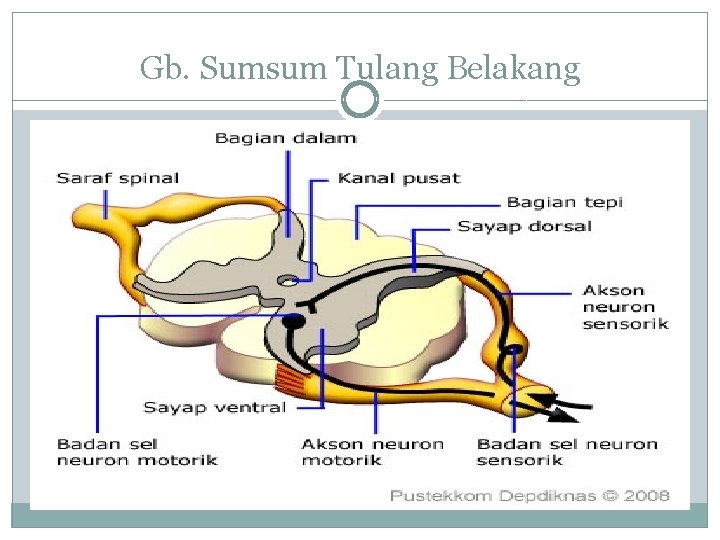

Sumsum Tulang Belakang Pengertian Letak Fungsi Struktur Dan Bagian Struktur Sumsum Tulang Belakang Medula Spinalis Manusia Lengkap

Sumsum Tulang Belakang Pengertian Letak Fungsi Struktur Dan Bagian Struktur Sumsum Tulang Belakang Medula Spinalis Manusia Lengkap

Sistem Saraf Pada Manusia Sistem Saraf Pusat Sistem

Sistem Saraf Pada Manusia Sistem Saraf Pusat Sistem

4 Fungsi Sumsum Tulang Belakang Pengertian Dan Strukturnya

4 Fungsi Sumsum Tulang Belakang Pengertian Dan Strukturnya

Pengertian Sumsum Tulang Belakang Fungsi Susunan Bagian

Pengertian Sumsum Tulang Belakang Fungsi Susunan Bagian

Sumsum Tulang Belakang Pengertian Struktur Fungsi Letaknya

Sumsum Tulang Belakang Pengertian Struktur Fungsi Letaknya

Struktur Dan Fungsi Sumsum Tulang Belakang Medula Spinalis Weschool Id

Struktur Dan Fungsi Sumsum Tulang Belakang Medula Spinalis Weschool Id

Fungsi Sumsum Tulang Belakang Mekanisme Penghantaran Impuls Pada Tulang Belakang

Fungsi Sumsum Tulang Belakang Mekanisme Penghantaran Impuls Pada Tulang Belakang